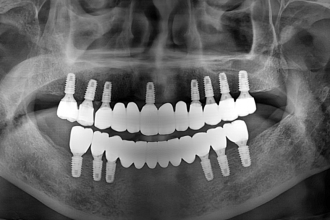

임플란트

굿프렌즈 치과 임상 케이스